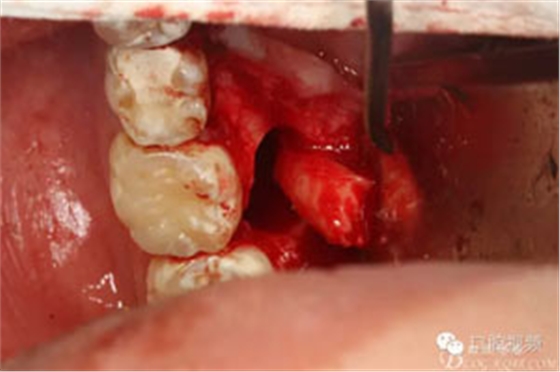

圖7.通過(guò)CBCT準(zhǔn)確定位,暴露35部分牙冠。

圖8.繼續(xù)去骨、暴露整個(gè)35牙冠。注意牽拉力度。

圖9.分牙、分別取出牙冠和牙根